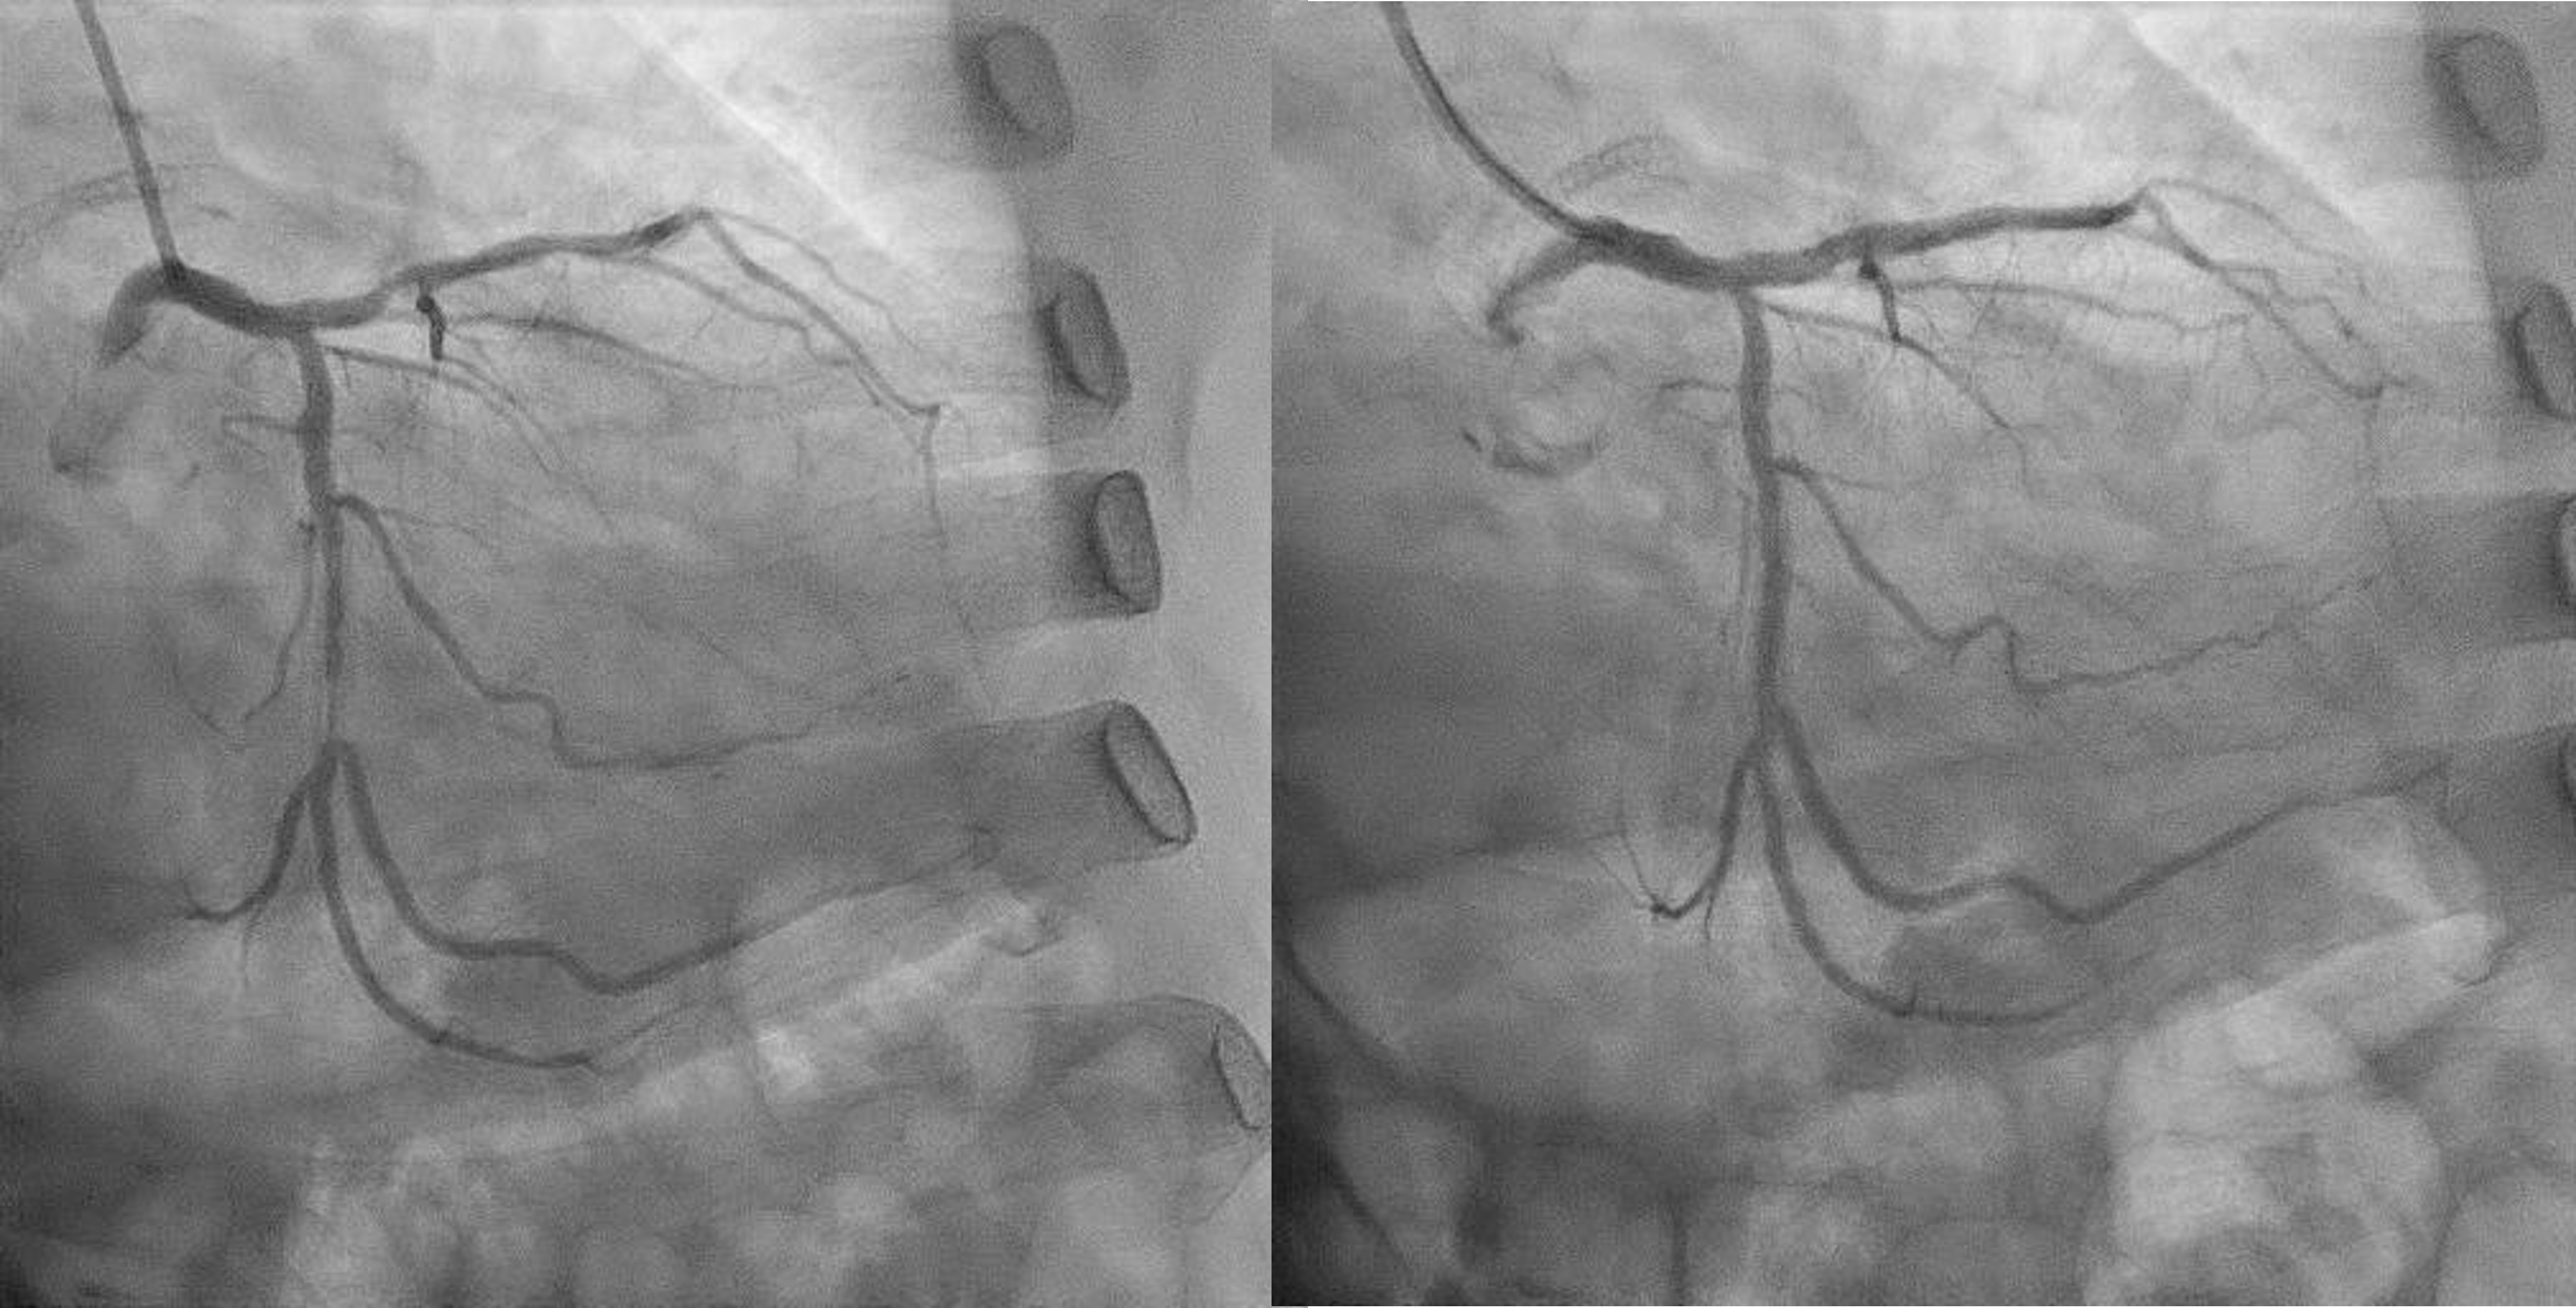

Now for staged PCI to RCA. Attempted engagement with a JR 3.5 6Fr via RRA.Challenges anticipated:1 subclavian tortuosity, noted from past angiography – needing gentle manipulation, avoid femoral access2 poor engagement due to ostium disease3 wiring from outside ( ¡®air-mail¡¯)Lesions are calcifed, diffuse, proximal(ostium RCA) and distal to stented segment - stent not covering ostium.Plan is to IVUS, prepare new lesions, prepare ISR segments then either hybrid DES/DEB or new DES all the way.

1 Initial predilatation with NC 3.0 > IVUS > Scoring 3.5 up till ostiumIVUS findings showed fibrocalcific+ nodular calcific plaques within and beyond stentRCA sizing was between 3.0mm till 4.0mm proximallyStent was long standing - likely adequately sized Smallest lumen was 1.83mm2 2 Just prior stenting another IVUS performedSmallest lumen (same as previous) improved > 4.0mm23 Long DES 3.0/48mm deployed > Postdilated with NC 3.5 then NC 4.04 Final IVUS performed, stents well opposed, ostium covered adequately but smalles lumen was 4.39mm2

Challenges:1 During PCI, ostium lesion causes BP dampening + ST elevations - catheter kept outside ostium during entire PCI2 Wiring was done from outside - 'air mail'ed into the RCA3 Long stent needed delivering - used 'buddy wire' technique to deliver this4 Findings exact ostium was tough - 'buddy wire' converted to 'sepal wire' for better outcome5 During postdilatation, the 'stubborn' nodule at the distal part of stent, was difficult to prepareEven after stenting, IVUS improvement only. Stent boost was used to delineate the calcific nodular area.